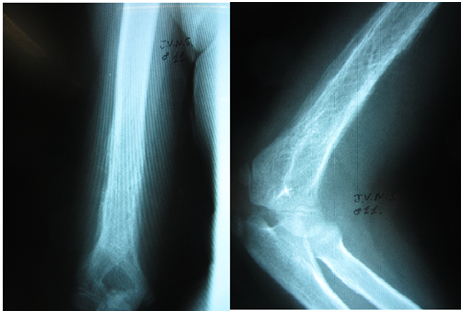

An 11-year-old male looked for medical assistance due to pain and swelling in his right arm, which had started three months earlier. Patient showed no other signs or symptoms. Swelling and warmth in the middle and distal thirds of the patient’s arm were found in physical examination. All laboratory tests fell within normal values, i.e., within reference range values, except for the LDH level, which was 280 U/L (normal LDH levels range from 100 U/L to 190 U/L). Radiological findings (Figures 1 & 2) showed permeable lytic lesions and “onion skin” periosteal reaction in the right humeral shaft. Thus, needle bone biopsy was indicated. Biopsy confirmed the presumptive diagnosis of Ewing’s sarcoma. After staging, which excluded the dissemination of the disease, the treatment protocol was started, which was neoadjuvant chemotherapy, associated to surgery and adjuvant chemotherapy. The oncologic resection procedure was performed 5 (five) months after the diagnosis - arthrotomy of the right elbow and humerus osteotomy at 22cm from the proximal extremity. In order to cover the bone defect, we opted for reconstruction with ipsilateral vascularized fibular autograft - a segment of 23cm of the right fibula with a vascular pedicle to the fibular artery has been resected. The medical team then performed a termino-lateral anastomosis to the brachial artery and termino-terminal anastomosis to the basilic vein (Figure 3). Clamping of the fibular graft under pressure in the humeral medullary cavity was the method of choice for graft fixation in the proximal end, and distally, the fixation was obtained with capsulorrhaphy of the head of the fibula to the elbow joint (Figure 4). The choice not to use a plate for proximal fixation was made in the intraoperative period due to the satisfactory stability obtained with the clamping of the graft in the humerus. Patient presented good postoperative evolution, with a satisfactory range of mobility in the limb which underwent surgery, and high patient-satisfaction ratings (Figure 5). Two fractures of the grafted bone segment (the first occurred 13 months after the surgery and the other one 32 months after the surgery) were the postoperative complications reported. Both of them were satisfactorily handled with conservative treatment, i.e., full cast.

Figure 1 Anteroposterior X-ray view of the right humerus and lateral view of the right elbow. Permeable lytic lesion and “onion skin” periosteal reaction in distal humerus can be seen.